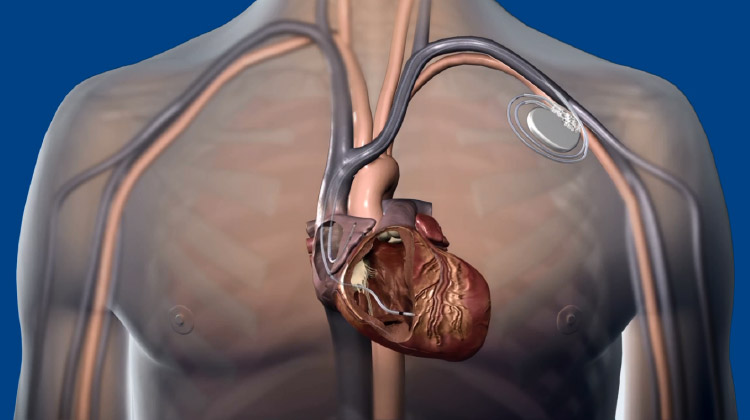

徐脈性不整脈の治療

心臓の動きが遅くなる徐脈性不整脈(洞機能不全症候群、房室ブロックなど)には、ペースメーカ植込み術を行います。従来は、心室の先端(右心室心尖部)に電極を置く方法が主流でしたが、この方法では心臓の動きが不自然になり、心不全や心房細動のリスクが高まることがわかっています。

そこで近年注目されているのが、刺激伝導系ペーシング(His束ペーシングや左脚ペーシング)と呼ばれる新しい方法です。これらは、心臓本来の電気伝導経路を利用してより自然に心臓を動かすことができる治療法です。

ペースメーカ埋込み術

Medtronic画像提供